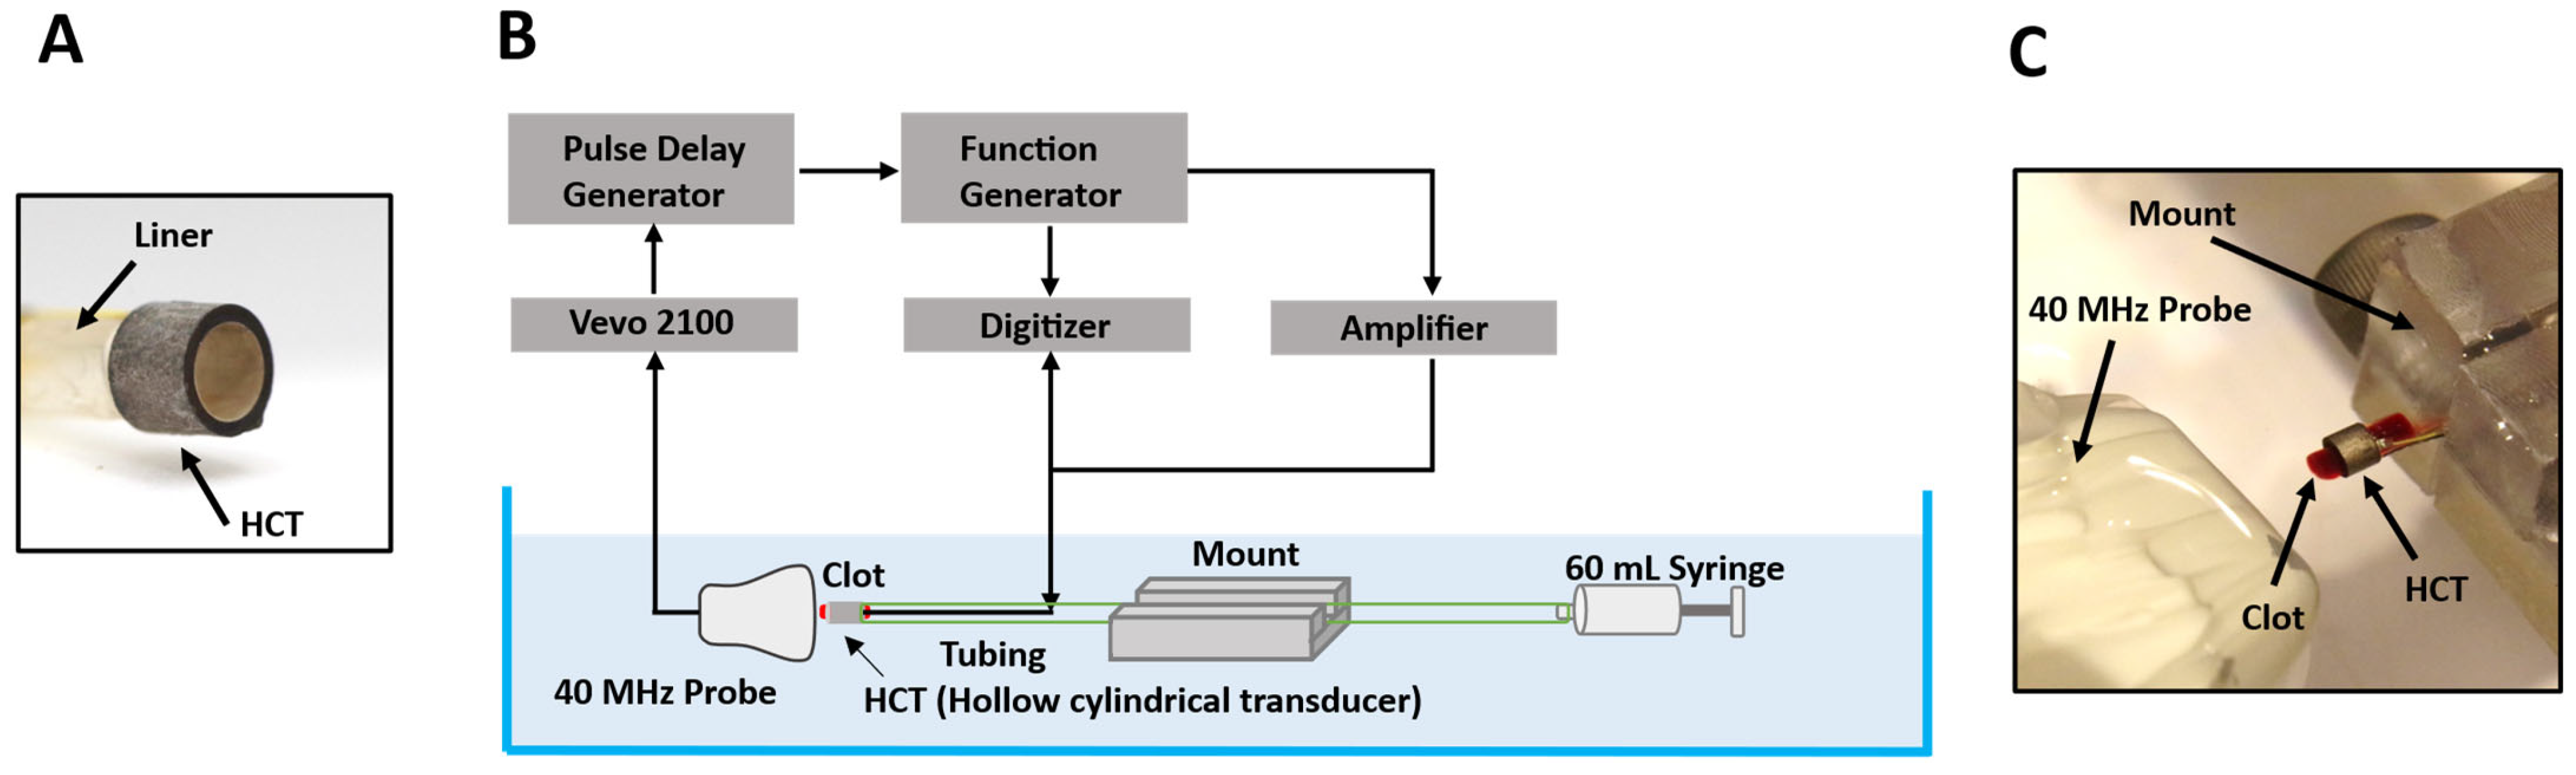

2.1. Transducer Configuration

2.2. Cavitation Observation with High-Speed Ultrasound Imaging

2.2.1. Experimental Configuration

2.2.2. Transmit Frequency Selections

2.2.3. Experimental Protocol